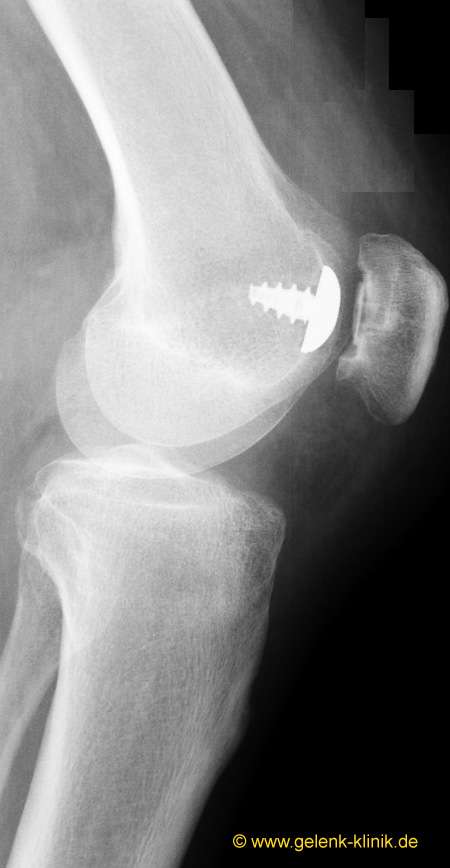

HemiCAP® retropatellare Oberflächenersatz-Prothese

In den letzten Jahren hat sich zunehmend die HemiCAP®-Prothese der Trochlea (Gleitrinne der Patella) durchgesetzt. Die HemiCAP®-Prothese muss nicht zementiert werden. Der Orthopäde verankert sie über eine Schraube stabil im Oberschenkelknochen. Die Rückseite der HemiCAP®-Prothese besteht aus einer knochenfreundlichen, rauen Beschichtung. Der Knochen der Trochlea (Gleitrinne im Oberschenkelknochen) wächst dann über die gesamte Fläche in die Rückseite der Prothese ein. Eine stabile Verbindung zwischen der Prothesenfläche und dem Knochen ist die Folge. Die Prothese hält damit auch sportlichen Belastungen stand.

Die in den Knochen einwachsende Befestigung sorgt für eine dauerhafte Stabilität des Implantates, auch ohne die sonst bei Prothesen übliche Zementbefestigung. Aus diesem Grund muss bei der HemiCAP®-Prothese – anders als bei zementierten Knieteilprothesen des Patellofemoralgelenks – keine Knochensubstanz aus dem patellofemoralen Gelenk abgetragen werden. Die oberschenkelseitige Metallkomponente gibt es in verschiedenen Ausführungen, um möglichst jeder Form der Trochlea (femoropatellare Gleitrinne) gerecht zu werden.

Aufseiten der Patella muss nicht zwingend eine Polyethylen-Gleitfläche eingesetzt werden. Ist die Knorpelfläche noch intakt, kann sie als Gleitpartner der Prothese dienen und bleibt erhalten.

Ist hinter der Patella ein starker Knorpelschaden vorhanden, ist auch eine Gleitpaarung mit einem PET-Implantat möglich. Patellaseitig wird ein gleitfähiges Plastikinlay aus haltbarem, hochvernetztem Polyethylen (PET) als Gelenkpartner angebracht.

Das HemiCAP®-Implantat kann den lokalen Arthroseprozess stoppen, ohne dass – wie bei zementierter Befestigung notwendig – ein Teil der Knochensubstanz des femoropatellaren Gelenks abgetragen werden muss.

Das Implantat kann minimalinvasiv, also mit einem kleinen Eingriff, eingebracht werden. Die Patienten sind bei dieser Methode häufig schon am Tag der Operation wieder mobil und auf den Beinen.